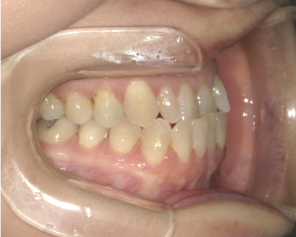

After Photo

After

主訴

かみ合わせ、反対咬合が気になる。

治療期間

9か月

料金

相談料0円、検査料33,000円、動的矯正治療費990,000円、保定装置料5,500円x2枚(必要枚数)

治療概要

前歯のかみ合わせが反対咬合だったため、下顎の歯を全体的に奥へ移動させ、前歯のかみ合わせを改善した。